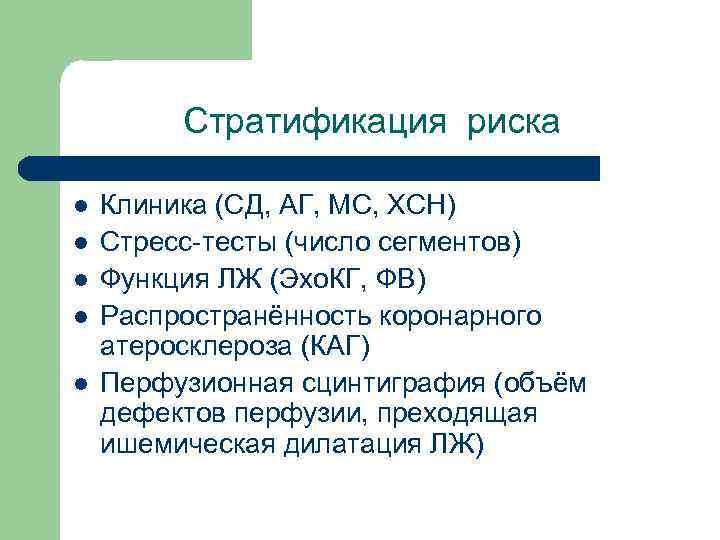

Стратификация риска l l l Клиника (СД, АГ, МС, ХСН) Стресс-тесты (число сегментов) Функция ЛЖ (Эхо. КГ, ФВ) Распространённость коронарного атеросклероза (КАГ) Перфузионная сцинтиграфия (объём дефектов перфузии, преходящая ишемическая дилатация ЛЖ)